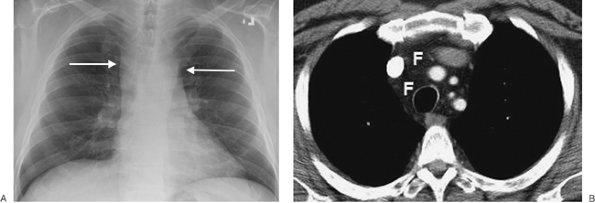

FIGURE 6-6. Mediastinal lipomatosis. A: PA chest radiograph shows an abnormally wide upper mediastinum with straight margins (arrows). B: CT scan shows abundant mediastinal fat (F).